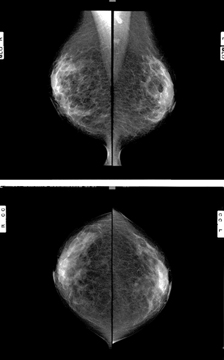

マンモグラフィ検査

当院のマンモグラフィ装置は1台で、人間ドック・熱海市乳がん検診・外来の全ての撮影を行っています。普通のX線撮影では写らない乳房の乳腺組織や脂肪組織、しこりを判別できるよう専用の機械を用いて乳房を板で挟みます。圧迫するため多少の痛みを伴う検査です。

圧迫することによって乳房の厚みが薄くなるため放射線の被ばくを減らすことができます。また乳腺を薄く伸ばし広げることで病変が写りやすくなるため、適切な圧迫が必要となります。ただしどうしても我慢できない痛みの場合は遠慮せずお声掛けください。

触診で分からないしこりが出来る前の乳がんでは石灰化を伴うことがあります。マンモグラフィはこの石灰化を写し出すことが可能であるため、乳がんの早期発見をすることができます。